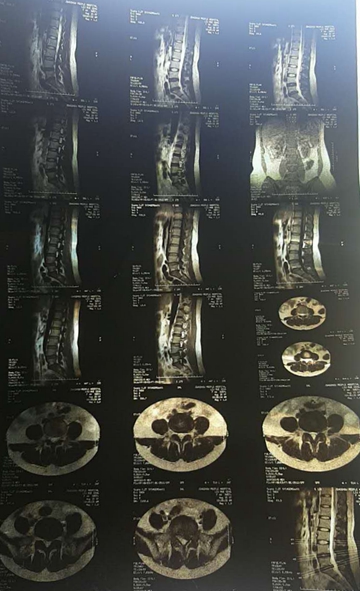

核磁轴位

核磁矢状位

2007年,刘女士,43岁,L5-S1椎间盘脱出0.8cm,胶州市人民医院外聘专家要求手术。不能行走,夜间痛性,主要表现为腿后侧。